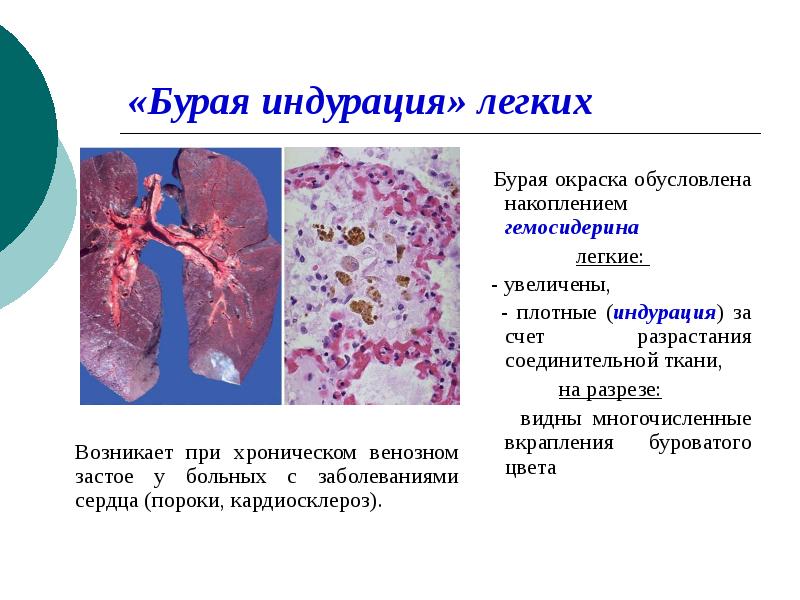

Карнификация Легкого: Микропрепараты и Диагностика

Раздел: Калейдоскоп образов